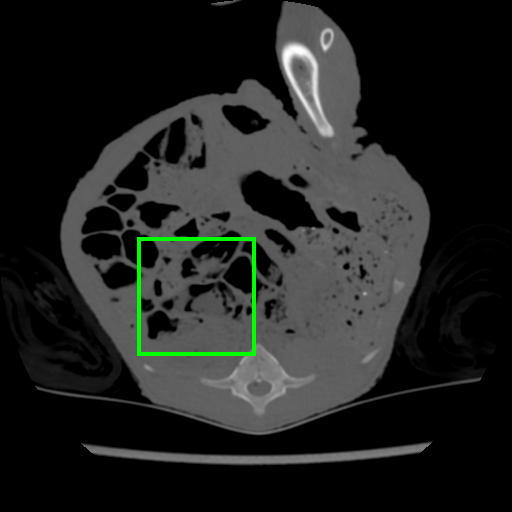

Task Generation. The CT database in [45] contains CT scans of a deceased piglet. The scans are produced using a normal dose of tube current (100%) and reduced doses. We use the doses of 10% and 5% because they include substantial amount of noise, where each dose set has 850 images of size . Following the data set protocol [45], 708 of those images are selected for training and 108 for testing. During training, each task consists of synthetic images generated by simulating reduced dose CT images by adding Poisson and Gaussian noise to the sinograms of the normal dose CT images, as in , where , , with denoting the Poisson distribution, representing the process to generate the sinogram or the fan-beam projected data [48] from the clean CT image , denoting the read-out electronic noise represented by the Gaussian distribution with mean and variance , and denoting the X-ray source intensity or a blank scan factor that controls the noise level. We create the tasks with , namely one per blank scan factor, where we use the following factors . Consequently, each factor contributes to the generation of a different task. To simulate the effect of the Gaussian noise, we add noise directly on the CT image . The Gaussian task is represented by Gaussian noise with , where denoting uniform distribution in . The result is the noisy image for and . Finally, we keep images for the meta-learning for each reduced dose set. The rest of the images are used for evaluation.

Model. We use a residual encoder-decoder architecture from [12] that has been proposed for low dose CT denoising [45]. The network consists of a 10-layer convolutional neural network with input and output sizes of . The activation functions are all ReLU, except for the last layer that is linear. The optimization algorithm is Adam [19] with learning rate . The inner loop has 20 epochs with mini-batch size 20. The outer loop runs for 1000 epochs with step-size and the number of fine-tuning samples .

Results. We evaluate CT-Scan denoising on tube current with doses and , where smaller percentage denotes more noise – results are summarized in Table 1. We generate from 4 to 8 Gaussian and Poisson tasks, with each task representing an individual noise model. Notice that we also applied Gaussian and Poisson noise, at the same time, on an image as another task, but the performance was not as good as sampling independently. In the case of task combination (e.g. 4 Gaussian and 4 Poisson), we equally sample tasks from both noise models. We attempted to generate less than 4 and more than 8 tasks, but there was not a considerable performance difference.

The same evaluation is performed for the supervised- and transfer-learning. Comparing with these two algorithms, it is clear that our approach delivers the highest PSNR. Although the results from transfer learning are closer, the difference is significant based on the t-test as we show in Sec. 4.4. Since this is the only experiment where we have access to a relatively large training set containing pairs of clean and real noisy data, we check the upper bound performance for our approach, which is the supervised learning performance using this large training set. Note that such full supervision violates one of our three assumptions mentioned in Sec. 1 – in particular, the one regarding the availability of a large number of training samples. Supervised learning achieves 40.28dB for and 38.84dB for , when trained with clean and real noisy training data. Our results in Table 1 indicate that we are close to this upper bound, although we train with synthetic training data. To further explore our approach, we meta-train it with clean and real noisy training data. Notably, our meta-denoising reaches 40.47dB for and 38.31dB for . This result shows the potential of meta-learning to become the standard training algorithm for the task of denoising. We present visual results in Fig. 1.